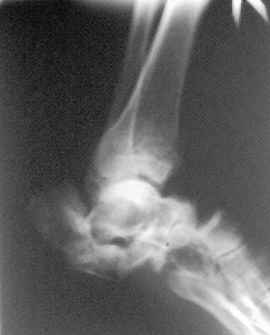

Травма 2,5 мес назад.Упал с высоты 3м. 46 лет.Средств для лечения в серьезных больничках нет! (ориентировочный запрос в региональном центре-2000 У.е минимум), снимки прилагаю. С уважением Д.Б.